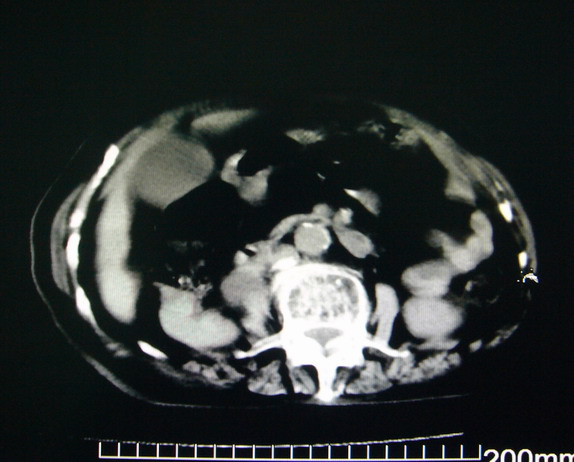

女:83y,转移性右下腹痛2小时,白细胞计数增高。

1.右侧肾盂扩大,肾盏无扩张,考虑:先天性肾盂变异可能性大。

2.胆囊扩张,考虑:胆囊炎。

3.阑尾区域可见以结节样高密度影,结合病史,考虑:阑尾结石,阑尾炎。

右下腹肠系膜增厚,结合病史支持阑尾炎.

右侧壶腹型肾盂可能,建议输路造影或增强

1.右侧肾盂扩大,考虑先天性肾盂变异或肾盂旁囊肿。

2.胆囊扩张,考虑胆囊炎。

3.阑尾区域可见结节样高密度影,结合病史考虑:阑尾结石、阑尾炎。